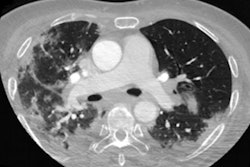

Due to its sensitivity for the detection of small and early infarcts, DWI-MRI is commonly used for evaluation of acute ischemic stroke, according to Hwang. ADC maps can also be used as a reference for acute infarction.

Seeking to develop a deep learning-based automated infarct segmentation model, the researchers first gathered DWI and ADC maps from 394 patients with an acute infarct treated at their institution between January 2015 and May 2019. Of these datasets, 216 were used for training and 24 were utilized for validation. The remaining 154 datasets were set aside for testing of the model.

The team elected to utilize a modified U-Net convolutional neural network in an ensemble approach in order to improve performance on small lesions, according to Hwang. After segmenting the infarct, the algorithm then measures infarct severity based on analysis of the ADC maps of the lesions.

Infarcts are thereby classified into one of four categories: no stroke symptoms, minor stroke, moderate stroke, and severe stroke. An ADC value of more than 620 was used as the threshold for the "no stroke symptoms" category; other category thresholds were set at intervals of 100 ADC values.